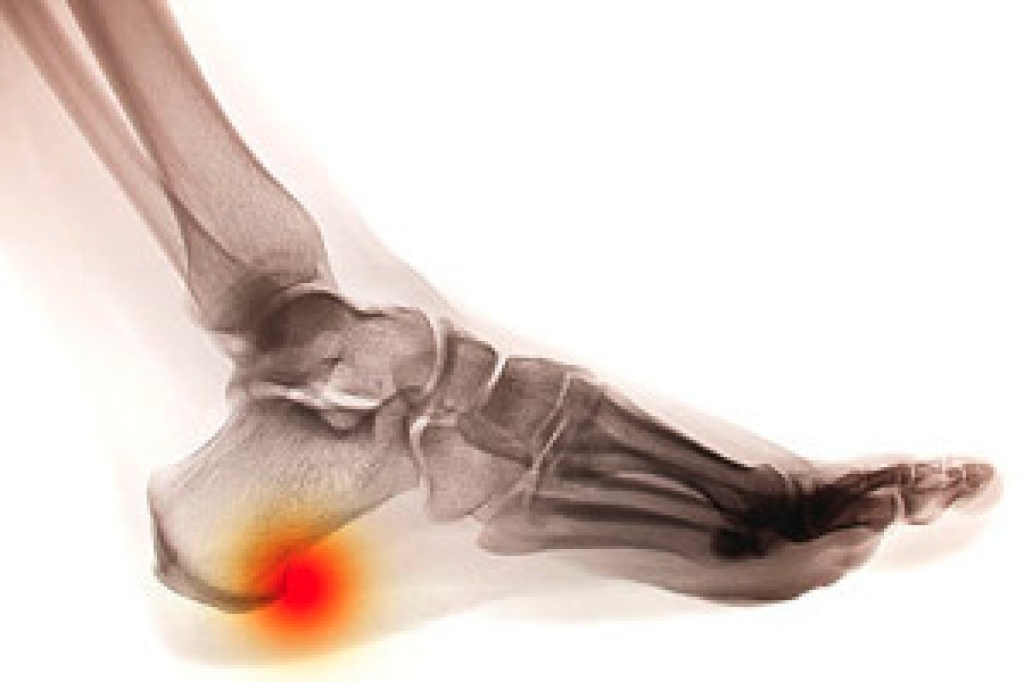

When there is excessive stress in the heel, new bone is formed to protect the heel against fractures. This is known as a heel spur and often feels like a bump in the heel. It typically begins as cartilage and then progresses into solid bone. They’re present in about half the population, although not everyone has pain. The most common cause of heel spurs is plantar fasciitis. If pain is experienced, it’s usually in the morning or after resting. Typically, after the first few steps, the pain will improve as the foot gets used to the movements. Certain exercises may also help relieve the pain. Placing the affected foot on a tennis ball while rolling it around may be beneficial in relaxing the muscles. Additionally, bending the knees while moving up and down may provide additional relief.

Heel spurs are formed by calcium deposits on the back of the foot where the heel is. This can also be caused by small fragments of bone breaking off one section of the foot, attaching onto the back of the foot. Heel spurs can also be bone growth on the back of the foot and may grow in the direction of the arch of the foot.

Older individuals usually suffer from heel spurs and pain sometimes intensifies with age. One of the main condition's spurs are related to is plantar fasciitis.